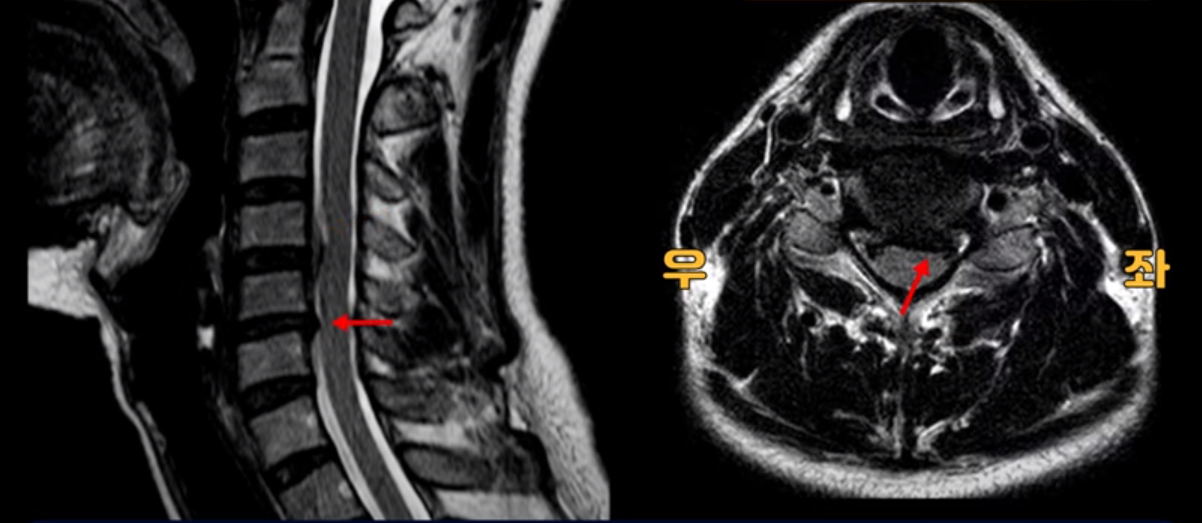

우선 이분 MRI를 보기 전에 이분 증상에 대해 말씀 드리면 오른쪽 팔저림과 방사통 및 어깨 통증이 있습니다. MRI를 보면 4번 5번에 디스크 파열이 보입니다.

밀려나온 디스크가 위로 타고 올라가 있는데 보시다시피 가운데로 밀려 나와 있습니다.

그래서 이게 오른쪽 통증의 원인일 수도 있고 아닐 수도 있습니다. 5번 6번은 왼쪽으로 밀려 나와있으니까 오른쪽 통증의 원인이 아닙니다.

그런데 이분 목을 보시면 여러 마디의 뼈가 퇴행이 진행되어 있습니다. 뼈가 깍두기처럼 각지고 예뻐야 하는데 끝이 조금씩 변형되어 뾰족하게 자라고 있습니다.

이런 게 협착을 일으킵니다. 그래서 우선 오른쪽 신경구멍 즉 추간공을 살펴보면 맨 위의 한마디를 빼고는 다 좁아져 있습니다.

특히 5번 6번 구멍이 가장 좁습니다. 이걸 협착이라고 합니다.

사실 여러 신경 구멍이 다 좁아져 있기 때문에 정확히 어느 마디가 방사통을 일으키는지 정확히 알기 어렵습니다. 그래서 만일 수술을 한다면 정확히 어느 마디가 진짜 원인인지 파악하지 못한 채 한다면 수술이 크게 실패할 수도 있습니다. 또한 이분처럼 여러 마디가 안 좋아서 수술한 마디의 위나 아래가 상태가 좋지 않으면 유합술 후 그 위나 아래에서 또다시 문제가 생기는 인접 분절 질환이 수술 후에 발생할 수도 있습니다. 이런 정도는 알아두는 게 좋습니다.